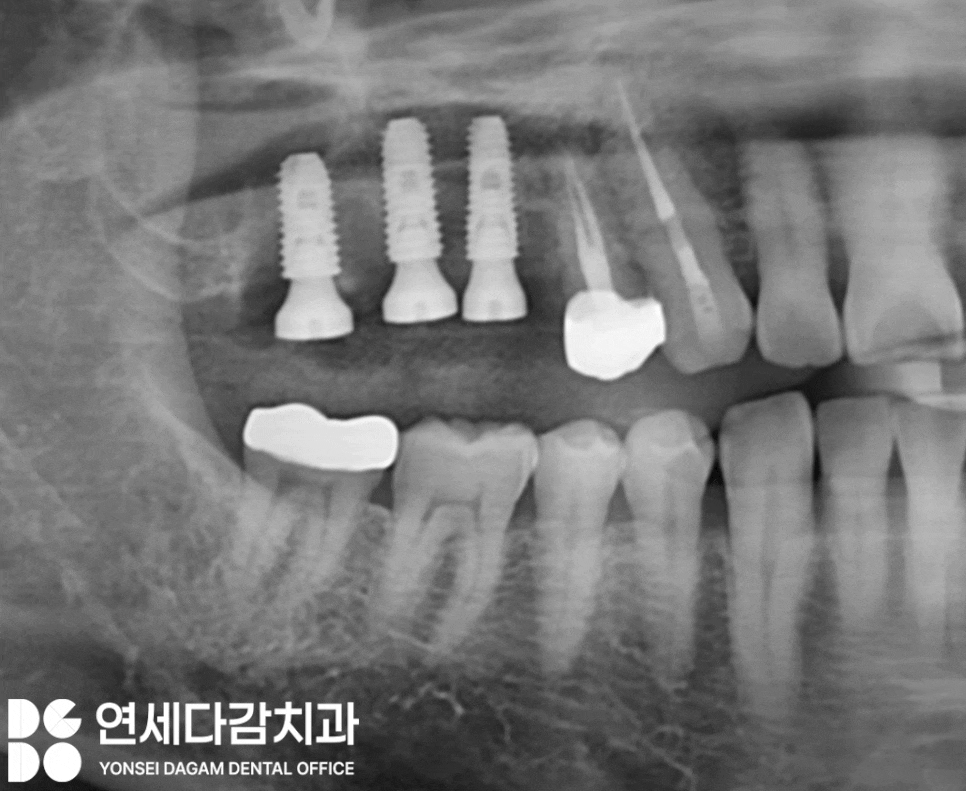

위 내용에 해당되는 케이스에서

사진에 표시한 부위를 살펴보면,

오른쪽 위 어금니 부위 치근 주변으로

심한 염증이 진행되고 있었습니다.

지지해 줄 뼈가 염증에 의해 소실되어

이가 흔들리고 있었으며

심한 악취와 고름이

배출되는 상태였습니다.

자세히 관찰해 보니

해당 어금니 중 하나는

뿌리 부위인 치근이

파절된 양상도 보였습니다.

더 이상 보존할 수 없는 상태로

발치 후 임플란트로 회복이

필요한 상황이었습니다.

그러나 해당 부위는 치근 부위와

상악동이 근접해 있는 위치이기 때문에

면밀한 분석 후

우선 문제가 되고 있던

어금니들을 발치했습니다.

이후 염증을 꼼꼼하게 없애기 위한

배농 작업을 시행했습니다.

그 후 소독을 통해

깨끗한 환경을 조성한 뒤,

사전에 분석하여 계획한

최적의 위치에 인공 치근을

식립했습니다.

그 결과, 초기 고정력이 양호한 상태로

수술을 무사히 완료할 수 있었습니다.